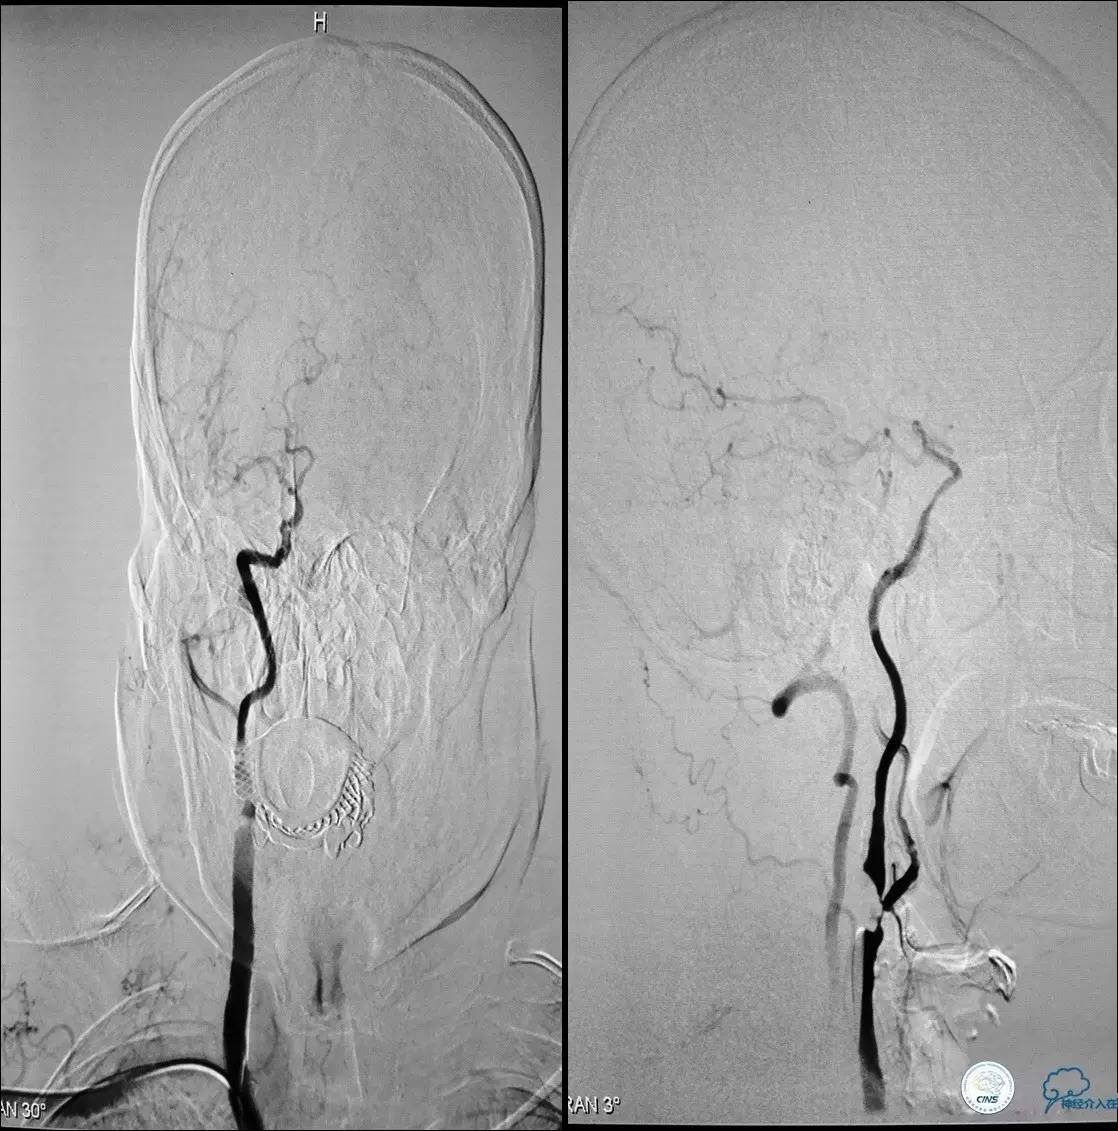

》辅助检查:颈动脉B超显示:左侧颈内动脉起始部狭窄 90%,右侧颈内动脉起始部80%。

颈动脉次全闭塞 术前评估

》头颅灌注+DSA!

头颅灌注: 注意两侧CBF CBV的对比。

DSA:注意侧支代偿。